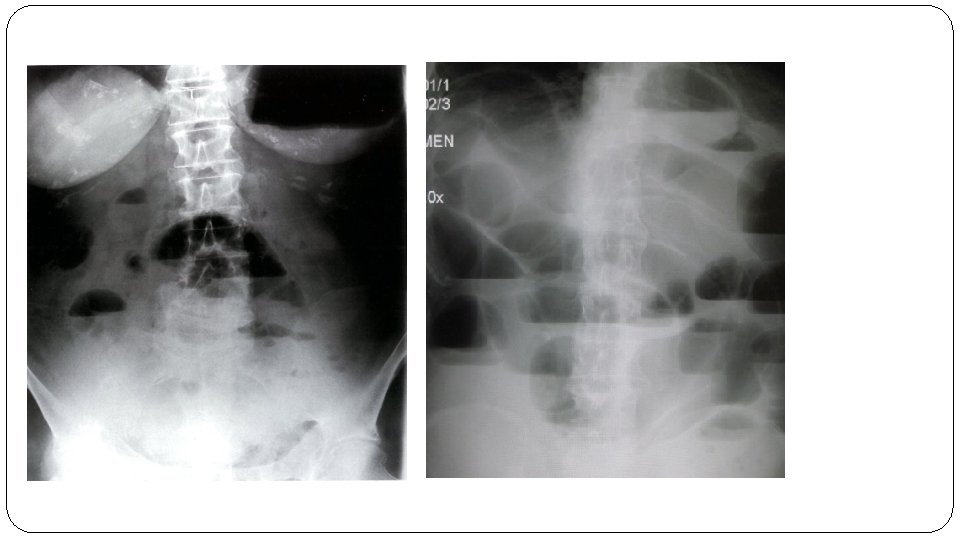

• Generalized adynamic ileus : Ø Dilated loop of large bowel ( white arrows ) Ø Dilated loops of small bowel ( dotted white arrows ) Ø Gases in rectum ( black arrows )